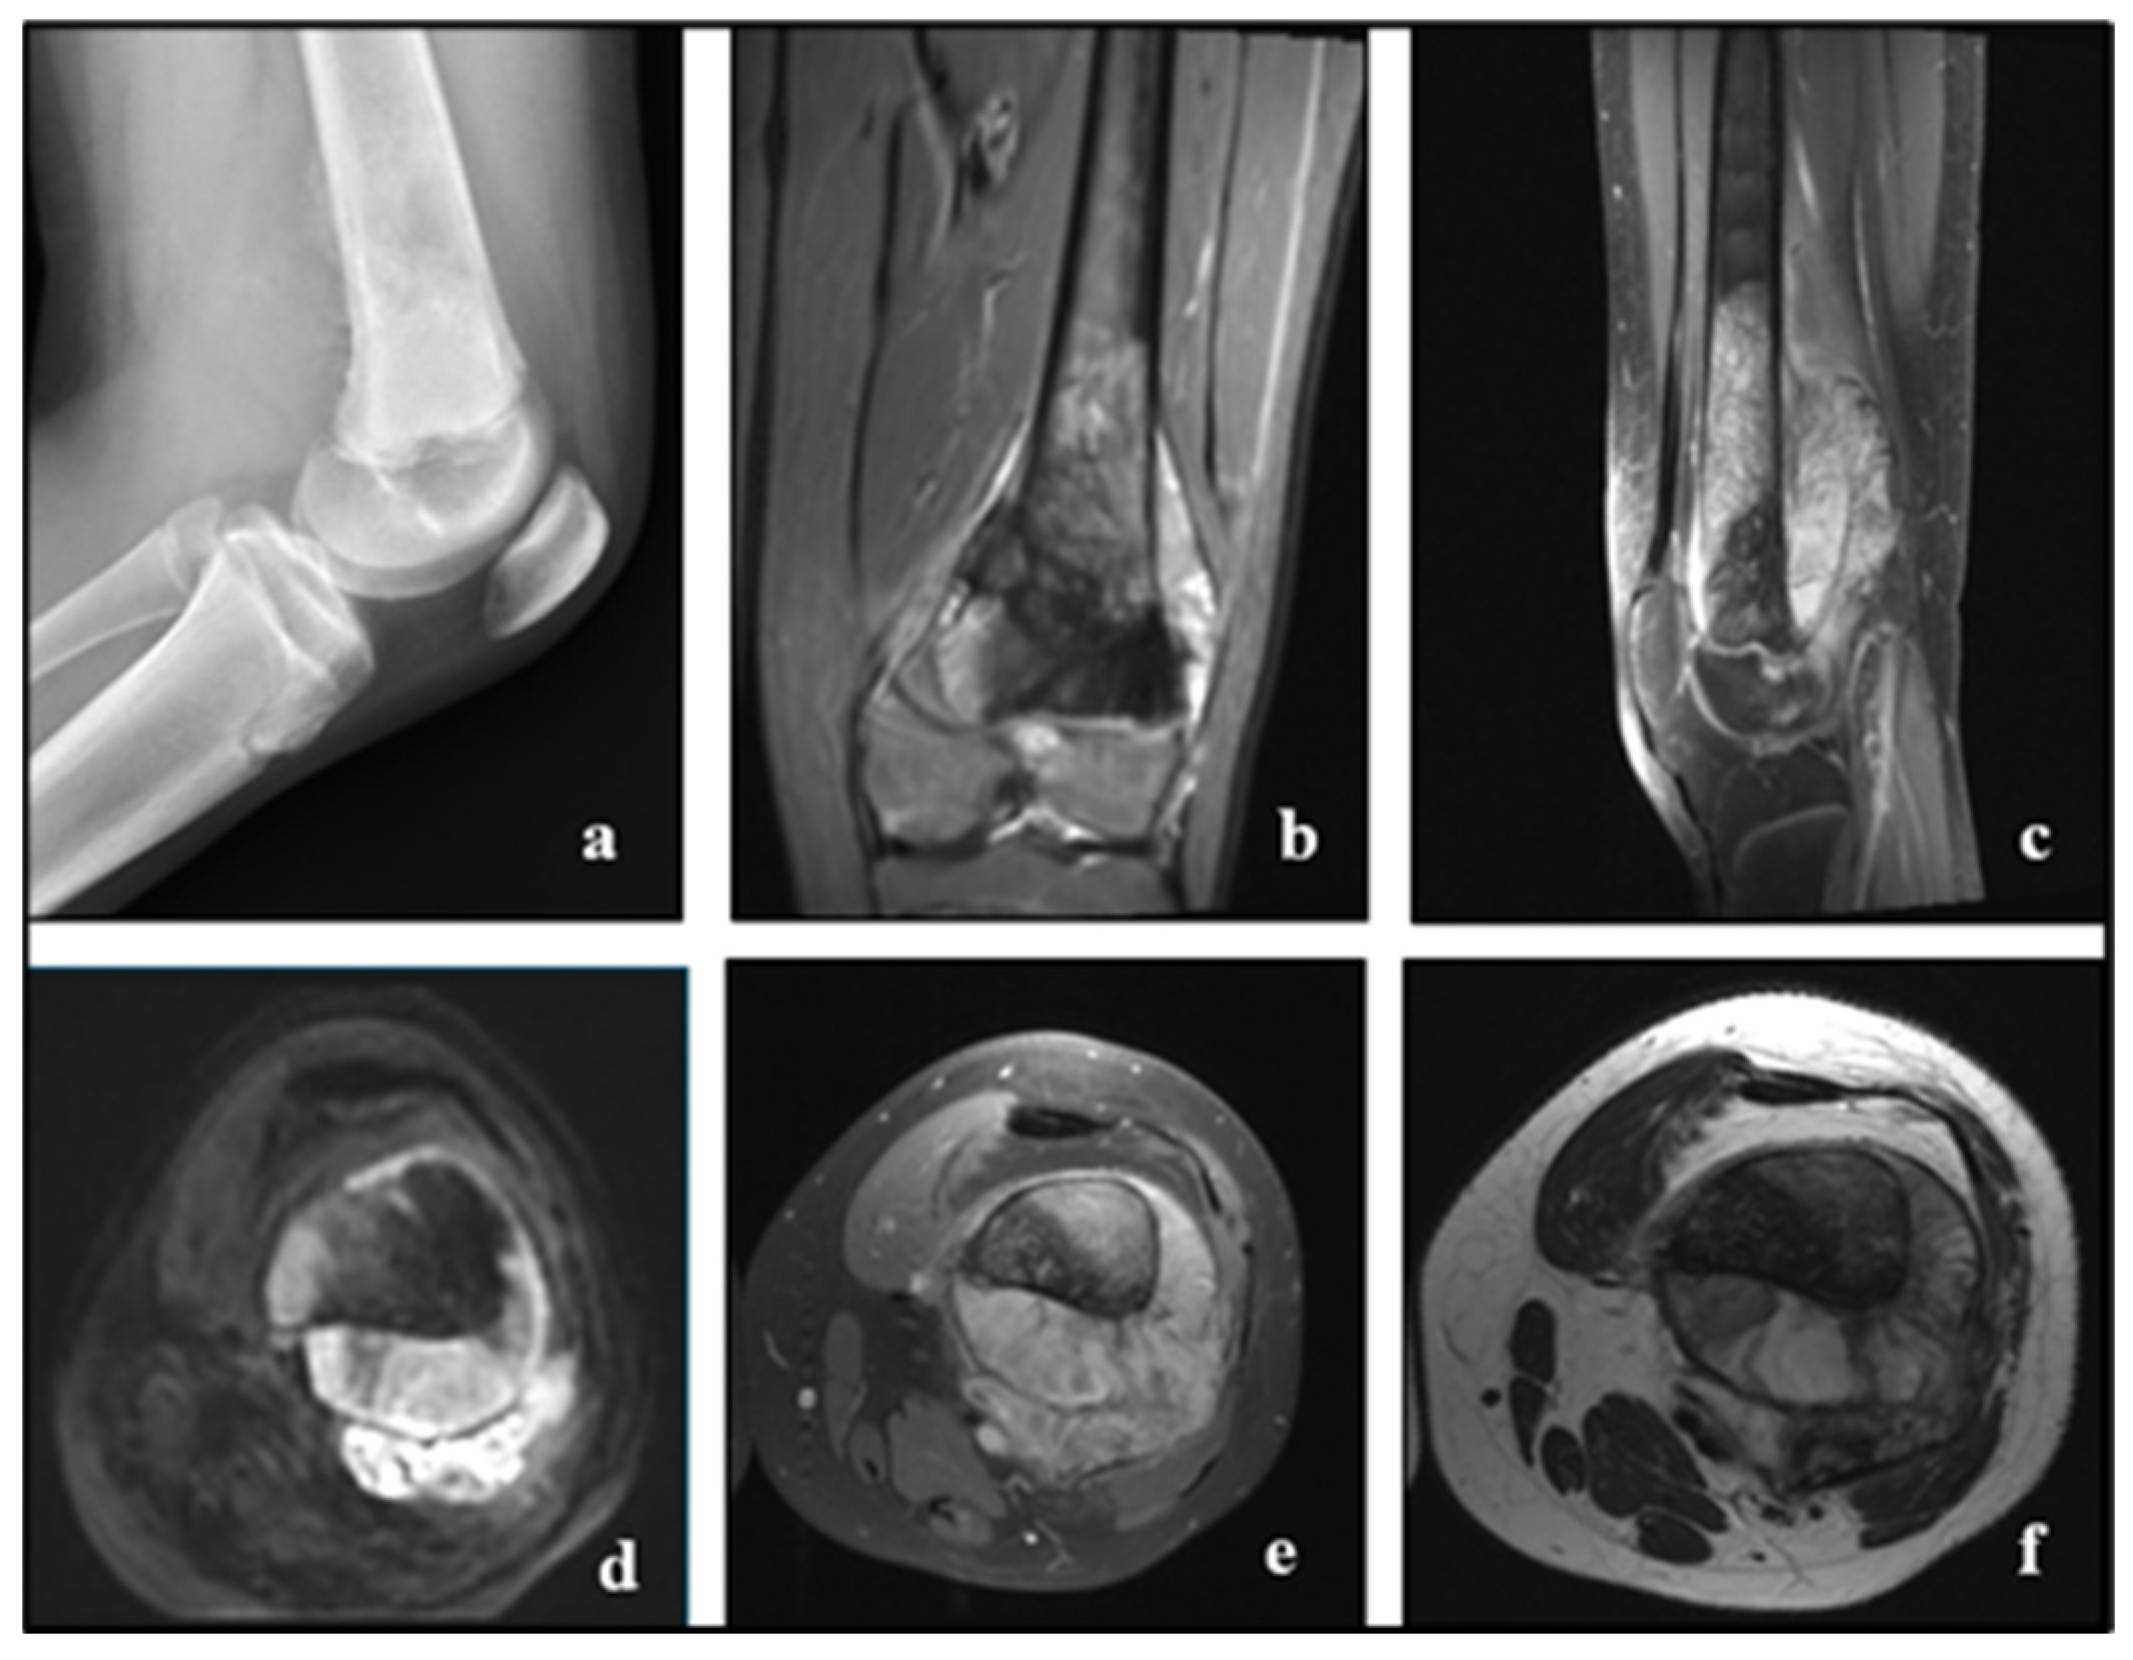

Figure 4. OS in a male of 15 years old: the radiography shows a bone lesion at the distal femoral metaphysis that does not cross the physis, extends in various directions, and causes destruction and loss of distinction between bone marrow and cortical bone, aggressive periosteal reaction of sunburst type and Codman’s triangle, and invasion of adjacent soft tissue (a). MRI (coronal STIR (b), sagittal T1 + C (c), axial DWI (d), axial STIR (e), and T2-W (f)) helps visualise the characteristics previously noted on the radiograph, showing tumor infiltration in the medullary canal and the metaphysis of the distal femur, not crossing the growth plate, with aggressive periosteal reaction (Codman’s triangle), invasion, and formation of adjacent soft tissue mass, restricted diffusion, and strong contrast enhancement after injection. Radiopaedia.org.

The most sensitive imaging technique for identifying and defining bone tumours, particularly when the medullary cavity is involved, is magnetic resonance imaging (MRI). Since MRI is the most effective local staging modality, it can be useful in the preoperative evaluation of patients whose conventional radiographs show an aggressive bone lesion (Figure 4).

The first-level investigation is represented by the X-ray, in which the radiographic aspect is that of a malignant tumour that originates inside the bone, rapidly destroying the cortical, the nascent sol appearance, the periosteal lift with the formation of the Codman’s triangle, the apposition of new bone in the tissues (Figure 1a,b).

The medullary canal is often involved (Figure 2). The growth of cartilage or physis can hinder its spread to the epiphysis.

MRI is very accurate in assessing the degree of extension of the tumour of the medullary canal and paraosteal soft parts from the presence of small bone metastases at a distance from the primary lesion without, however, allowing a reliable demonstration of tumour calcifications.